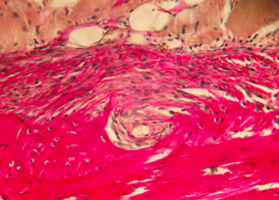

Морфологическое и лабора-торное обоснование приме-нения комбинированных трансплантатов при костной пластике челюстей

Экспериментальное исследование. Изучение морфогенеза после заме-щения дефектов нижней челюсти смесью лиофилизированной алло-спонгиозы и “аллогенного гидроксиапатита” в соотношении 1:1 и 3:1.

Экспериментальное исследование. Изучение морфогенеза после заме-щения дефектов нижней челюсти смесью лиофилизированной алло-спонгиозы и “аллогенного гидроксиапатита” в соотношении 1:1 и 3:1.